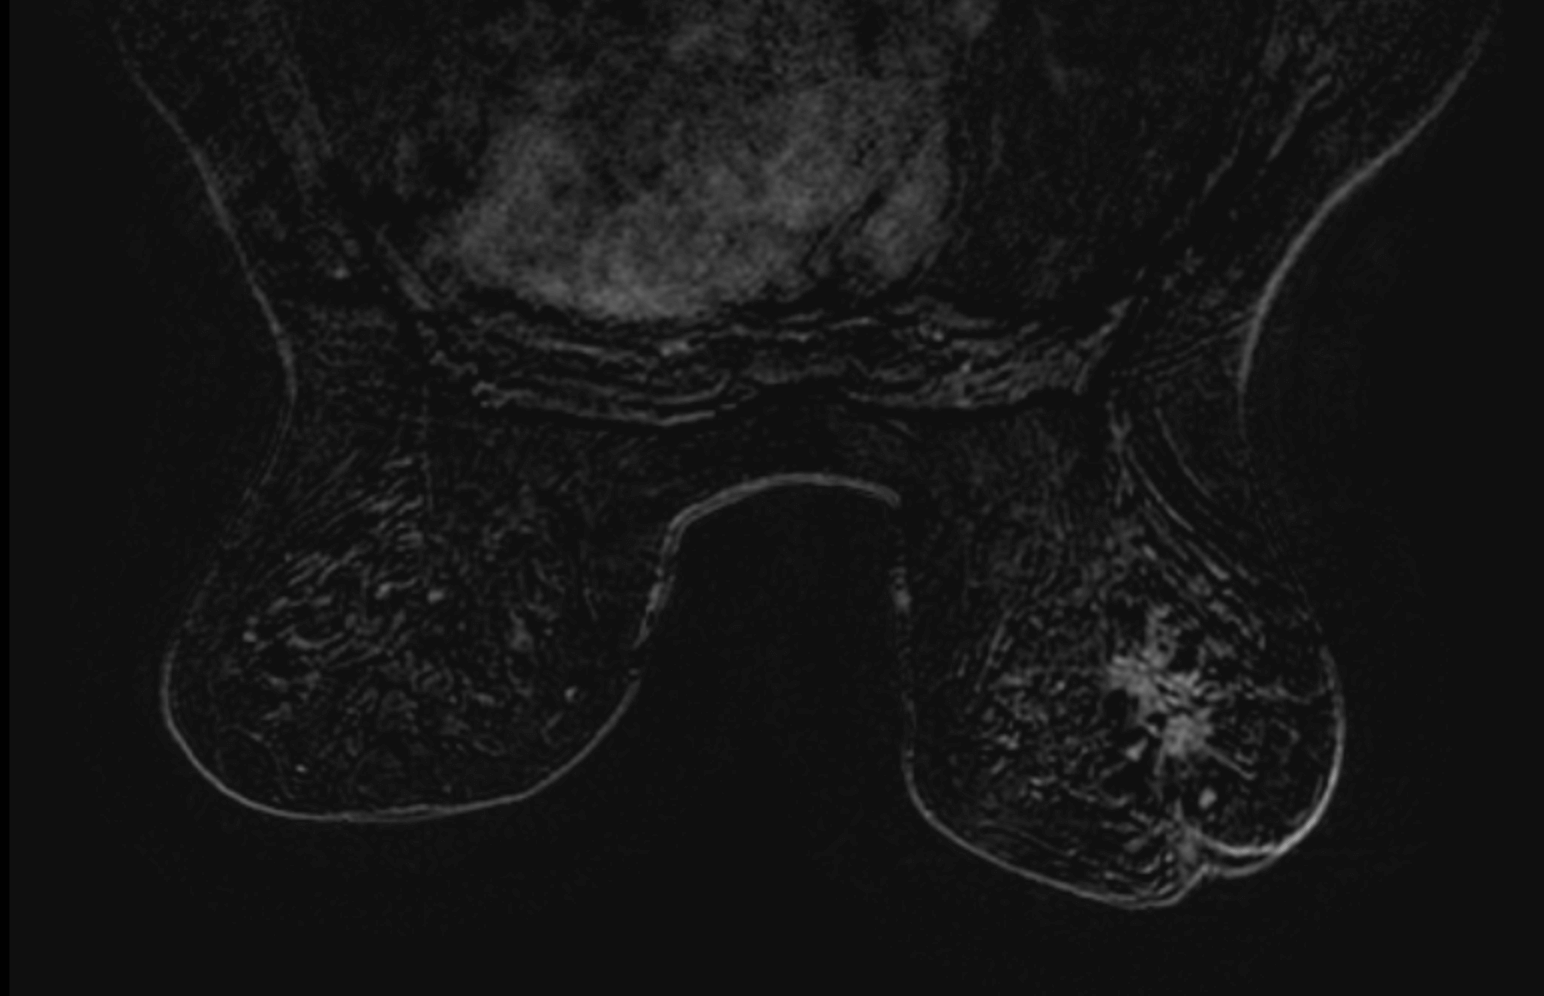

The mass was found on ultrasound and measured 20mm. MRI shows a large mass.

With a very high score, the AI could have alerted the first radiologist, fortunately the patient has asked for a second opinion…

Biopsy: invasive ductal carcinoma grade 3